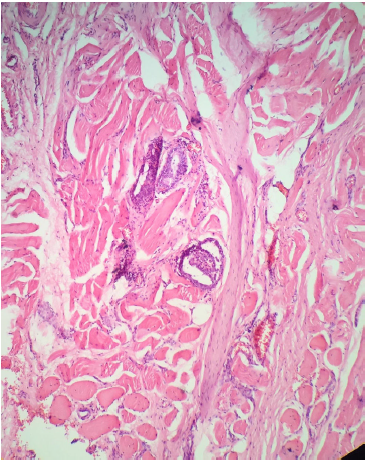

La ETE está definida como el compromiso de la lesión tumoral primaria a los tejidos blandos peritiroideos. La glándula tiroides en general no tiene una cápsula fibrosa anatómica bien definida, por lo tanto en muchos casos el tejido "peritiroideo" (que en general es tejido adiposo, vasos sanguíneos o pequeños filetes nerviosos) entra íntimamente en contacto con el parénquima haciendo que se diagnostique la ETE fácilmente si hay tumor en estos tejidos (fig. 2).

Figura 2 Ausencia de cápsula tiroidea. Transición abrupta del tejido tiroideo normal al tejido adiposo extratiroidea (H&E 10x).

Sin embargo, esta invasión aparentemente "obvia" no se considera para algunos autores como una verdadera ETE y sugieren que más bien la invasión del músculo esquelético en los lóbulos laterales del tiroides es la principal clave diagnóstica para evaluar la ETE. Esto a diferencia del istmo, que normalmente puede estar en contacto o incluso dentro de la misma glándula (fibras musculares esqueléticas del músculo de Soemmrring o musculo elevador del tiroides), por lo cual la interpretación de la ETE en un nódulo del istmo requiere una estricta correlación con los hallazgos intraoperatorios y de los hallazgos en el examen histológico en busca de invasión en otras estructuras del cuello, tales como cartílago laríngeo o esófago15.